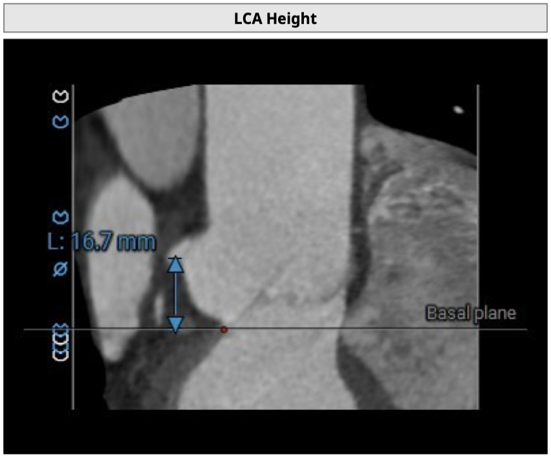

左冠开口高度16.7mm